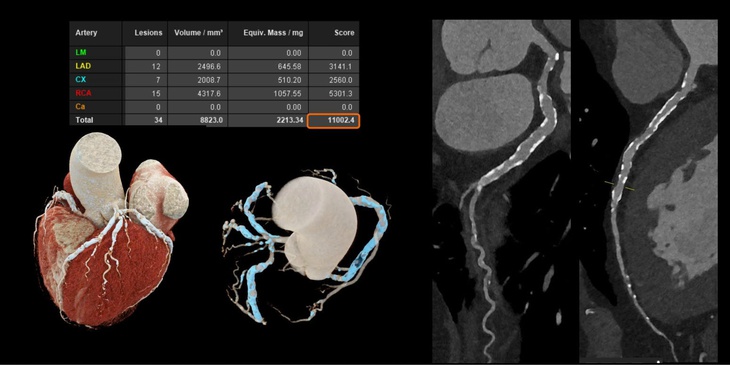

Với các bệnh tim mạch, đặc biệt ở những bệnh nhân đã đặt stent hoặc có mạch vành bị vôi hóa nặng - vốn là những trường hợp khó đánh giá bằng CT thông thường. Công nghệ này cho phép hình ảnh rõ ràng hơn đáng kể.

Nhờ đó, bác sĩ có thể quan sát chính xác lòng mạch và các mảng xơ vữa, ngay cả khi bệnh nhân có nhịp tim cao hoặc loạn nhịp mà không cần sử dụng thêm thuốc hỗ trợ.

Hình ảnh mạch vành cho thấy độ rõ cao hơn, giảm nhiễu và giúp đánh giá chính xác hơn - Ảnh: Siemens Healthineers